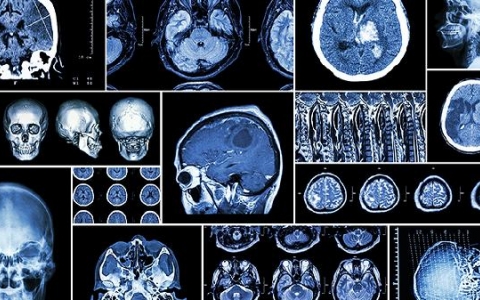

脑瘤晚期为什么不说话

脑瘤晚期患者不能说话常是由于脑瘤发展,压迫或者损伤了与说话有关的神经中枢所导致,比如在人类的语言中枢当中,运动性语言中枢,或者叫说话中枢,往往仅靠中央前回的下部

脑室内出血有哪些症状

脑室内出血有哪些症状?脑室内出血在脑病中越来越常见,可发生在任何人身上。发病后,患者的大脑健康受损,进而出血、眩晕、呕吐,甚至影响患者的日常生活。提醒大家彻底了

脑梗死的危害有哪些

脑梗死的危害分个人和社会两个层面。第一.个人层面,由于脑梗死会导致下列功能功能损害,使病人的生活能力、工作能力、社会适应性明显下降甚至丧失;脑梗死后遗症分为阴性